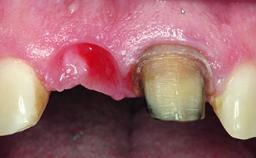

Replacement of an Upper Right Central Incisor with Root Resorption: Ridge Preservation, Early Placement of an RC Bone Level Implant

A 49-year-old female patient was referred for implant therapy to replace the upper right central incisor (tooth 11). The tooth had been assessed by an endodontist who diagnosed a vertical fracture of the root. The tooth had a hopeless prognosis and needed to be extracted. The patient was healthy and was not taking any medications. She was allergic to penicillin. The patient had high esthetic demands but her expectations were realistic. The extraoral examination revealed no facial asymmetries. The right temporomandibular joint demonstrated an opening click but was otherwise asymptomatic. The lip line was high with a significant gingival display.